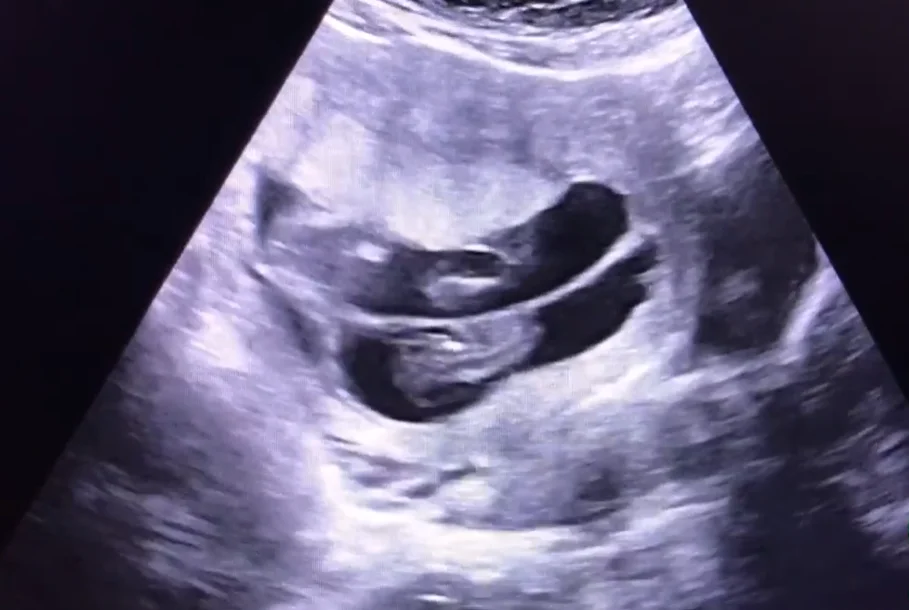

Song thai hai nhau - hai ối (Dichorionic Diamniotic Twins - DCDA)